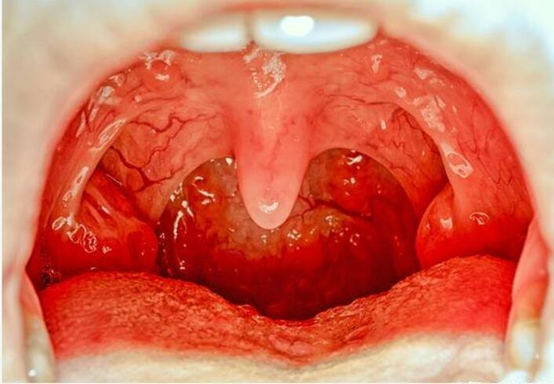

1.化脓性链球菌引起的急性咽炎、急性扁桃体炎。